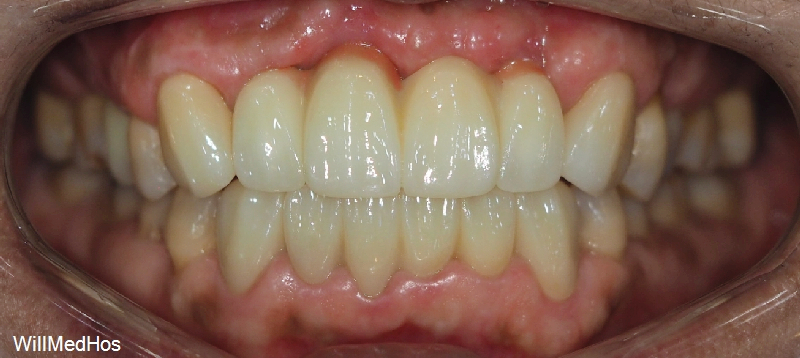

최종으로 치료 마무리된 환자분의 모습입니다.

전체 치료 소요 기간은 총 6개월 되었습니다.

환자분께서는 너무 만족 한다며 원장님께 매번 감사하다고 말씀 해주시는데요.

저희도 환자분의 자신있는 미소와 말씀들을 보고 들으니 감사할따름입니다